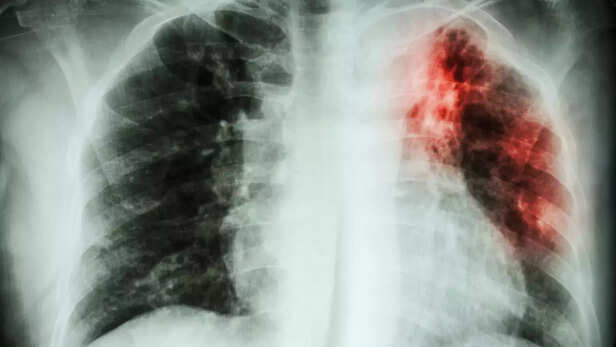

हमारे शरीर का प्रतिरक्षा तंत्र हर समय रोगजनक जीवाणुओं से लड़ता रहता है। लेकिन, प्रतिरक्षा तंत्र जैसे ही कमजोर होता है, तो बीमारियां हावी होने लगती हैं। ऐसी ही, बीमारियों में से एक है टीबी की बीमारी। जिसे तपेदिक या क्षय रोग के नाम से भी जाना जाता है। टीबी का पूरा नाम ट्यूबरक्लोसिस है, जो 'माइकोबैक्टीरियम ट्यूबरक्लोसिस' नामक जीवाणु से होता है। टीबी रोग मुख्य रूप से फेफड़ों को नुकसान पहुँचाता है। हालांकि, टीबी का वायरस आंत, मस्तिष्क, हड्डियों, जोड़ों, गुर्दे, त्वचा तथा हृदय को भी प्रभावित कर सकता है।